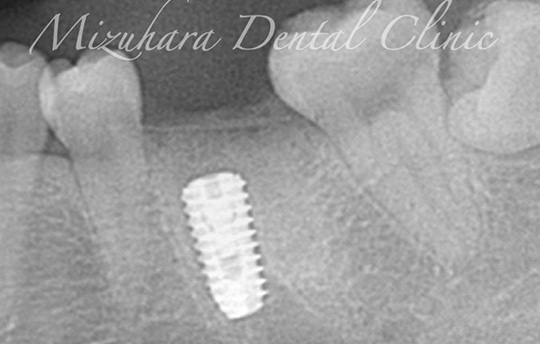

治療中

期間 インプラント治療:4ヶ月

(先に抜歯をしてリッジプリザベーション(骨を追加する手術)を行い、3ヶ月後にインプラント治療開始)

費用 オステムインプラント(臼歯):440,000円

リッジプリザベーション:66,000円

治療内容 インプラント治療と抜歯したと同時にリッジプリザベーション(骨を追加する手術)を行った。